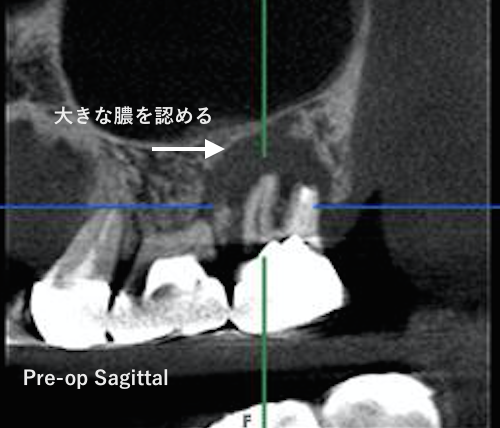

CT撮影すると上の一番奥歯の根尖とその手前の歯の根尖に膿が溜まっているのが観察されました。

こんなに大きく膿が溜まっていると普通は抜歯と宣告されるでしょうね。